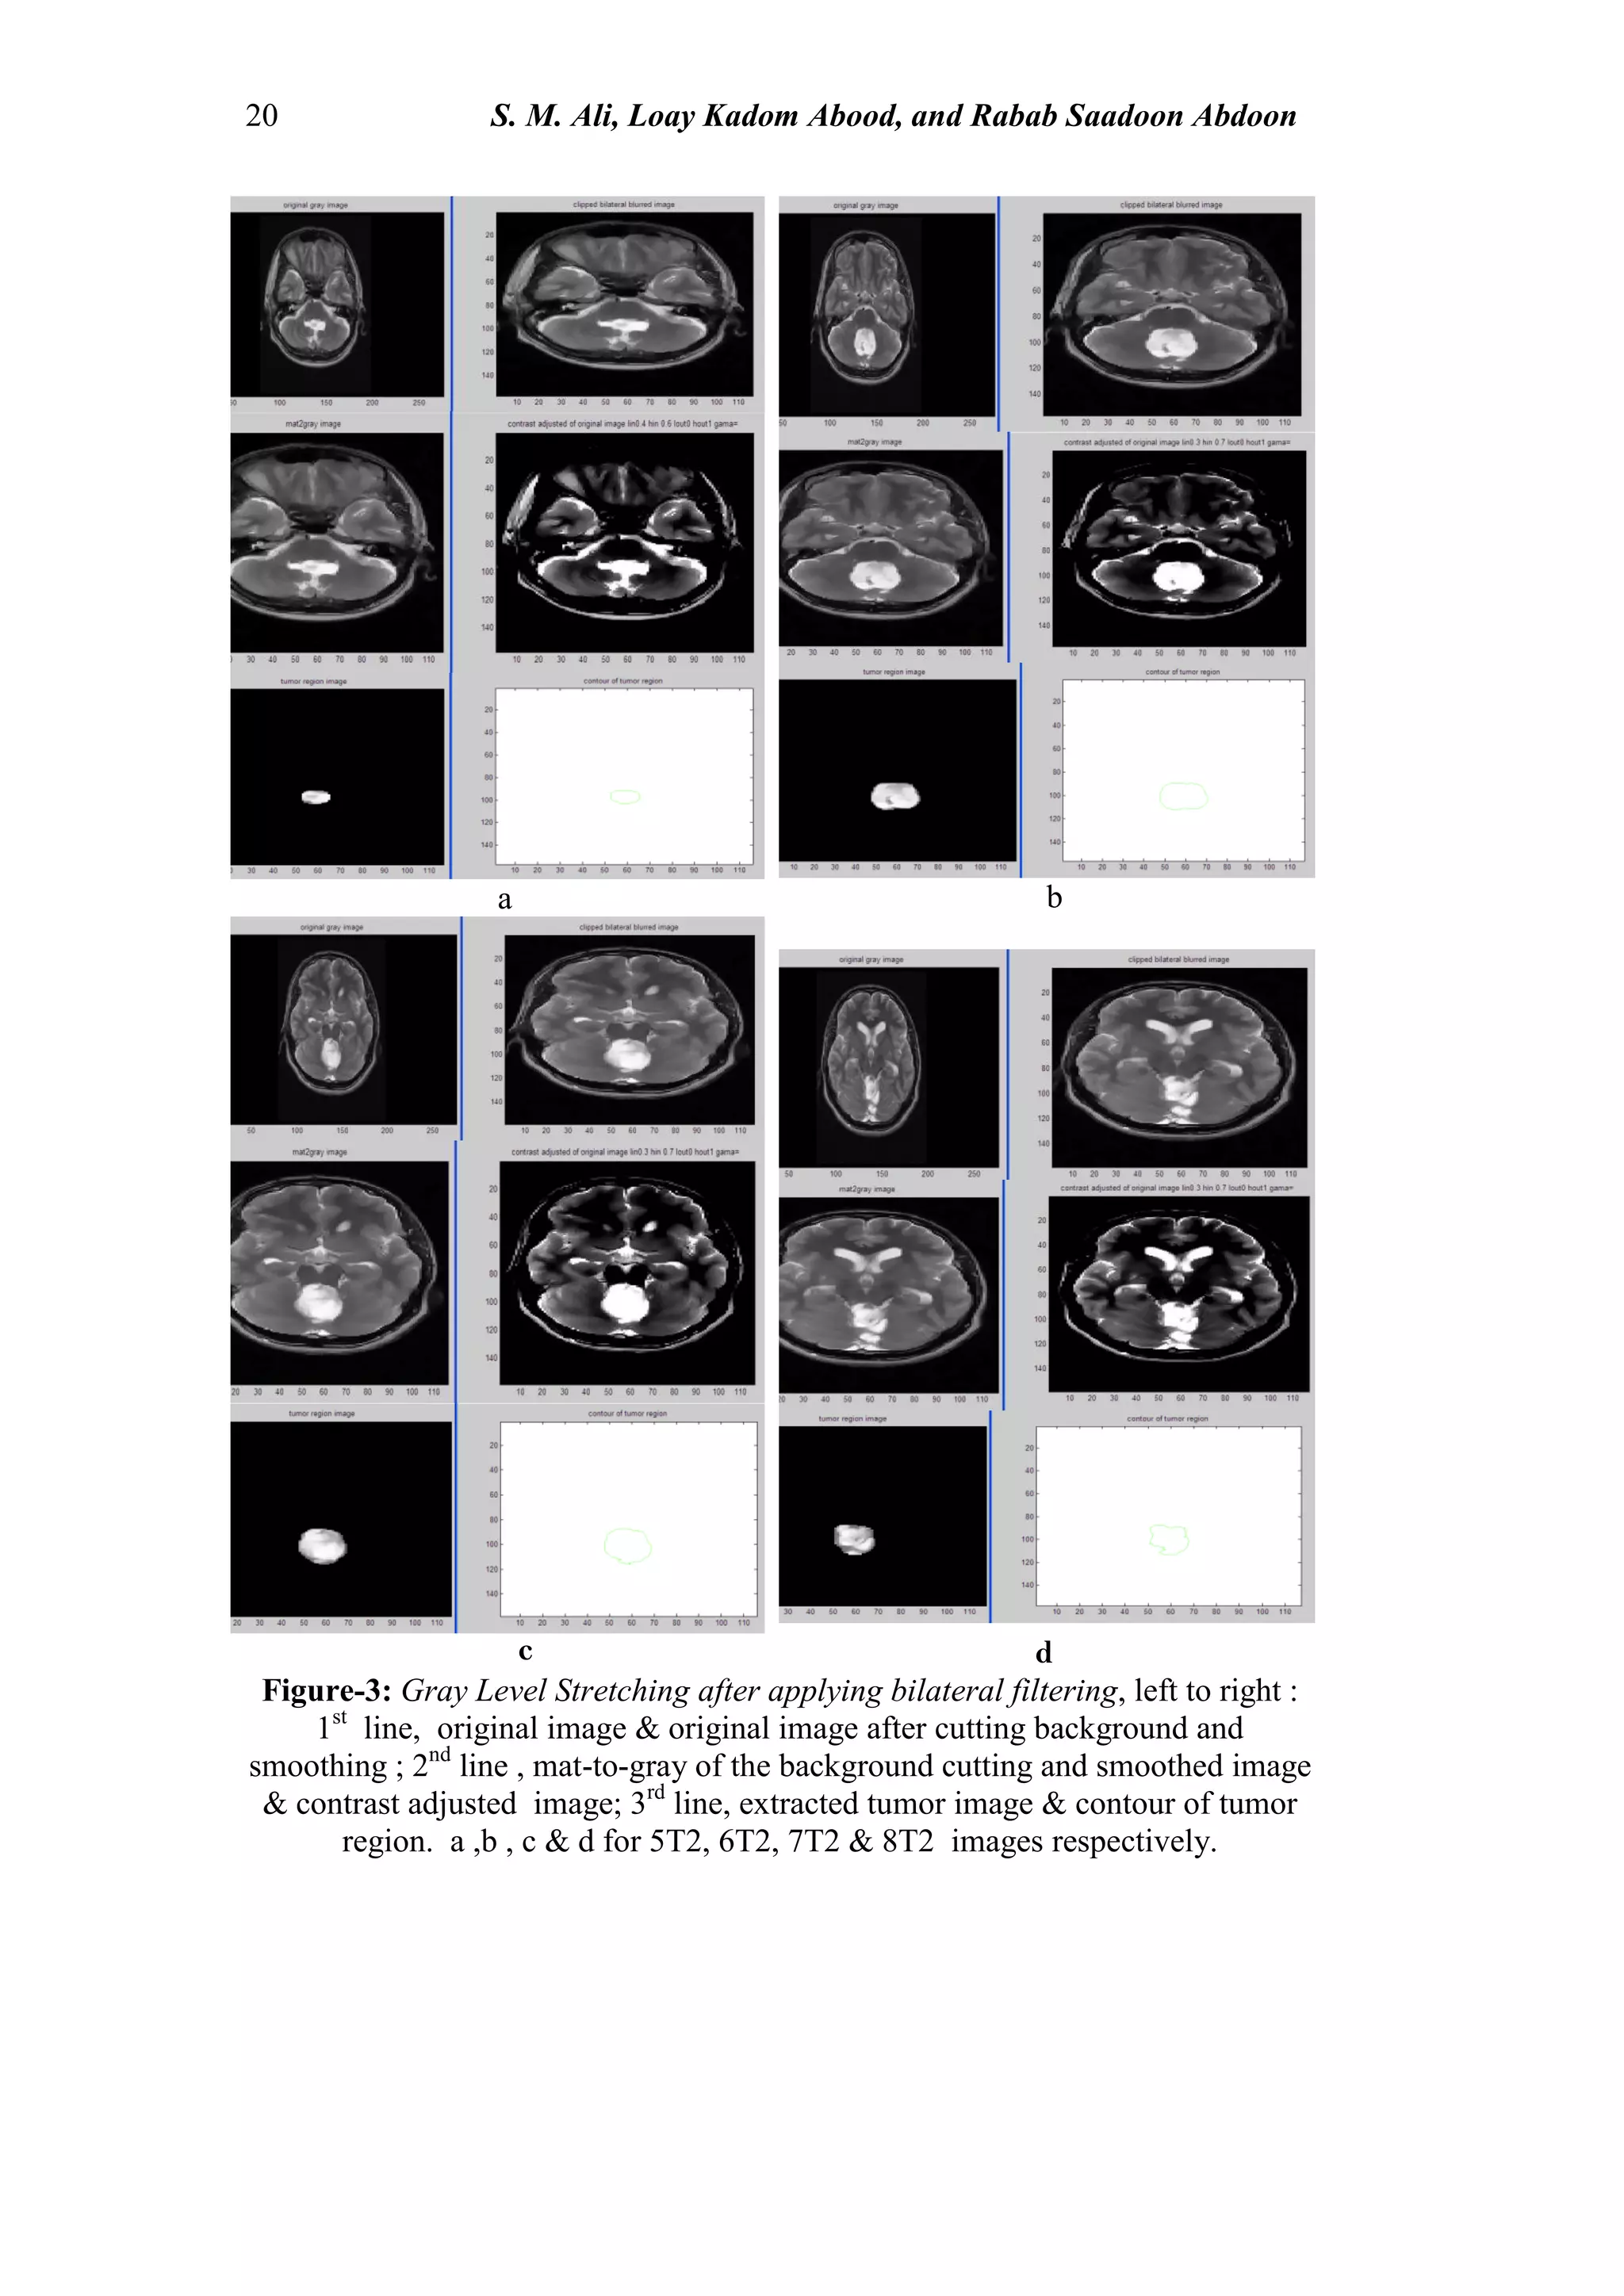

Figure-3: Gray Level Stretching after applying bilateral filtering, left to right :

1st

line, original image & original image after cutting background and

smoothing ; 2nd

line , mat-to-gray of the background cutting and smoothed image

& contrast adjusted image; 3rd

line, extracted tumor image & contour of tumor

region. a ,b , c & d for 5T2, 6T2, 7T2 & 8T2 images respectively.